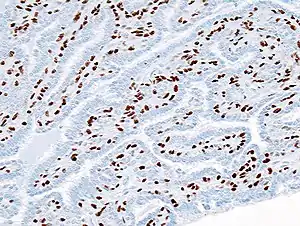

Papilomas intraductais da mama são lesões benignas com uma incidência de aproximadamente 2-3% em seres humanos.[1] Distinguem-se geralmente dois tipos de papilomas intraductais. Os de tipo central desenvolvem-se perto do mamilo, são geralmente solitários e aparecem por volta da menopausa. Por outro lado, os de tipo periférico são vários papilomas que aparecem na periferia das mamas e em mulheres mais jovens. Os de tipo periférico estão associados a um maior risco de malignidade.[2]